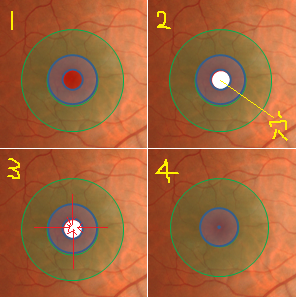

?正常な網膜です。中心部の赤い部分の網膜には、物を見るための視細胞が沢山集まっています。その周りの青にも、視細胞がありますが、赤に比べると数が少なくなります。緑はさらに見え方が落ちる部位です。

?黄斑円孔で、赤の部分の網膜が硝子体に引っ張られて断裂し、無くなってしまうと、視野の中心部が欠損、見たい部分が見えなくなってしまいます。

?手術の効果で、青や緑の網膜を中心部に引き寄せます。

?青の部分の網膜が、視野の中心部の視界を担うようになります。

赤に比べて、青の網膜は、視細胞の数も能力も乏しくなります。この青の網膜が中心部の見え方を担当するようになるので、どんなに回復しても「視力が悪い」、「感度が悪い」、「少し暗く見える」などが残り、完全に元通りという事はあり得ないのです。

青に比べて、緑はさらに感度が悪いのですが、黄斑円孔の穴が大きく、青の部分まで無くなってしまった症例では、緑が中心部の役割を担うために、さらに後遺症が大きく残ります。